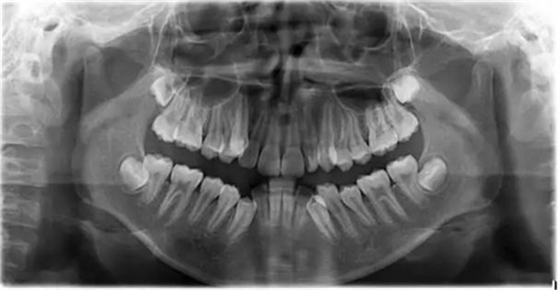

1500866161_694151.jpg1500866311_947305.jpg

此病例主要考慮的是垂直骨面型,矢狀骨面型,前牙覆合覆蓋及尖牙關(guān)系,側(cè)貌